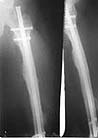

This young individual(a seond year medical student at that time) was brought to us four years ago with subtotal amputation of right hemipelvis and fracture left femur. He was treated with emergency right hemipelvectomy, emergency permanent sigmoid colostomy,ileal conduit for urinary diversion and external fixation for left femur. After he was stable and off ventillator interlocking left femur was done.

1) Should we attempt removing the Interlocking nail now (Sun nail, marketed by Mathy's Medical India for Synthes) ?